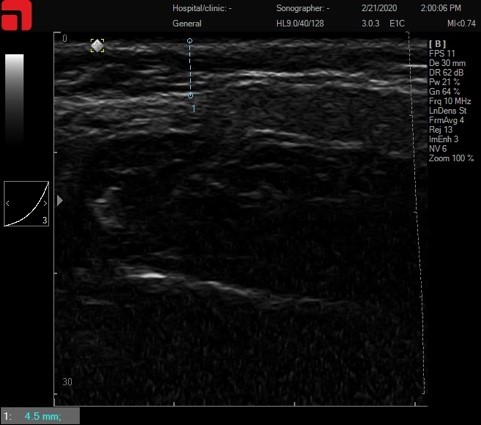

Соединительная ткань при сильном надавливании

Рис. 2. Соединительная ткань при сильном надавливании.

Как видно на данном слайде, интенсивное надавливание на манипулу распластывает ПЖК, приближая СМАС-слой к поверхности кожи, делая его более доступным для лифтинговых насадок (3 мм M7 и 4,5 мм D4). Но из-за высокой плотности дермы и выраженной ПЖК, у данного пациента этого будет недостаточно. Это редкие ситуации в клинической практике, но они возможны. В таком случае дополнительно приподнять СМАС-слой, распластав мягкие ткани, можно изнутри, установив интраоральную каппу или заложив ватные диски между зубами и слизистой оболочкой щек.